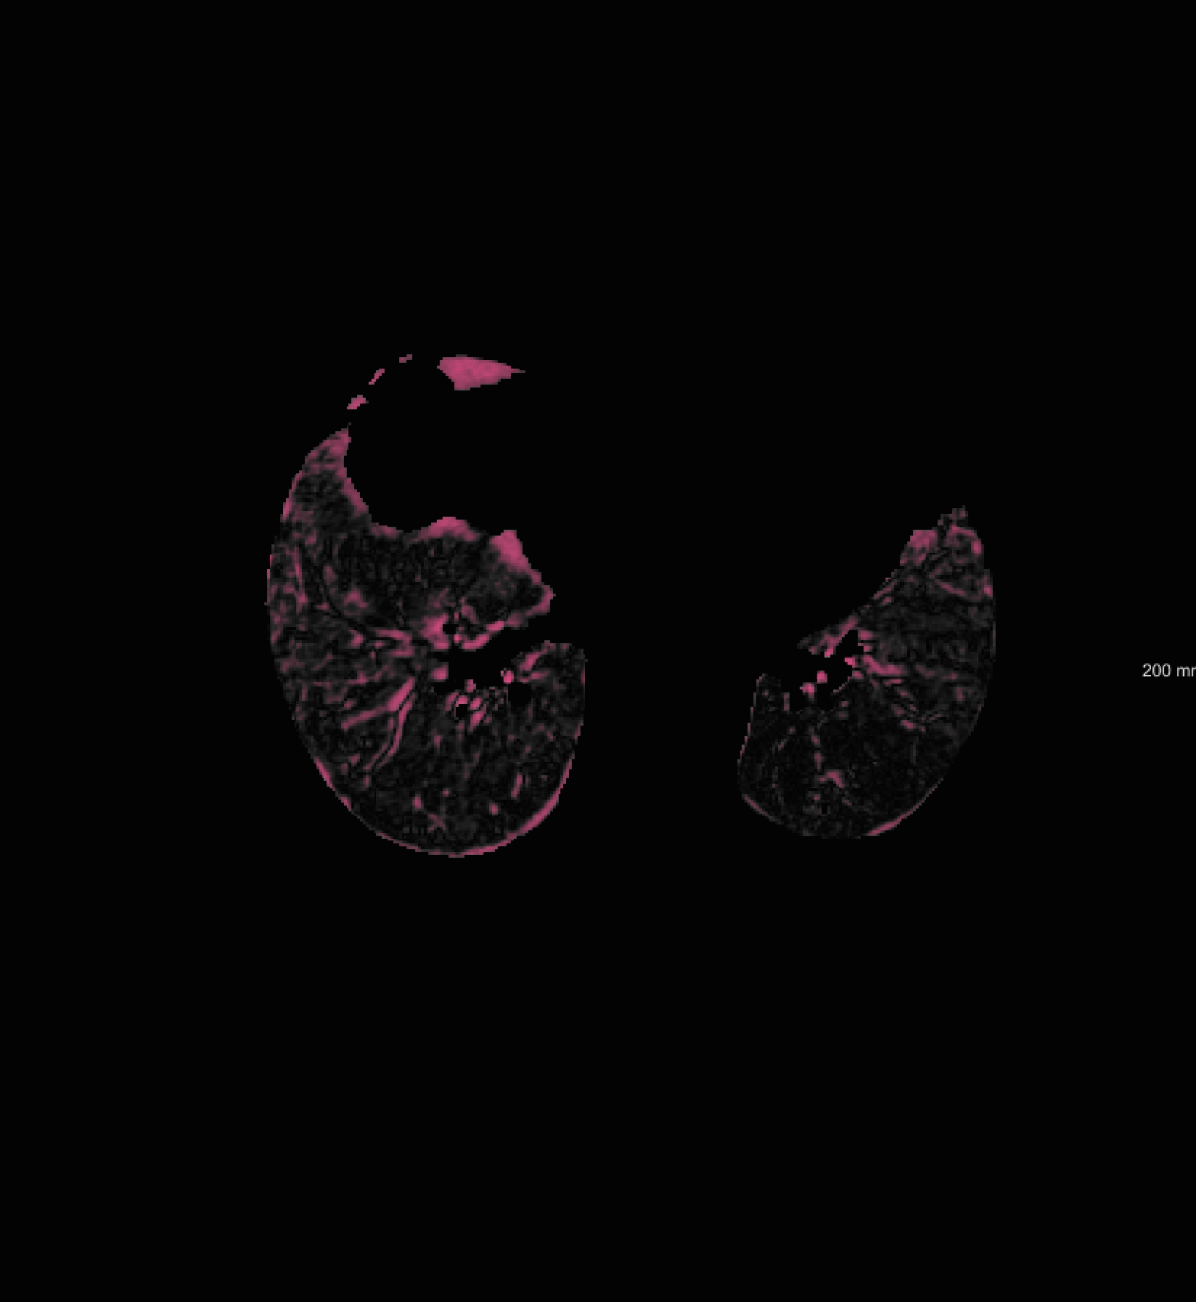

For the DIR-Lab-4DCT database, a comparison between RegNet and affine, B-spline (three resolutions), an advanced conventional registration method using sliding motion (Berendsen et al., 2014) and three other CNN-based methods (Eppenhof and Pluim, 2018; de Vos et al., 2019; Sentker et al., 2018) is available in Table IV. It can be seen that training with “S+M” improved performance slightly with respect to just “S”. Adding the respiratory motion category improved performance substantially, as these are inhale-exhale pairs; this is predominantly caused by the patients where the TRE after affine registration was still quite large. An example visualization is also available in Fig. 5(f), showing that adding the respiratory motion category can align images better in the diaphragm region. The advanced conventional registration method that leverages sliding motion (Berendsen et al., 2014) is still better than RegNet. Note that RegNet was not trained on the DIR-Lab-4DCT data, similar to Eppenhof and Pluim (2018); Sentker et al. (2018). However, de Vos et al. (2019) and Eppenhof and Pluim (2018)-DIR methods were trained on the same database but using cross-validation to report the results. Also note that the results reported in Sentker et al. (2018) are averaged over all phases of DIR-Lab-4DCT (T00 to T10), while the results of other CNN methods (including RegNet) are reported between the maximum inhale and maximum exhale phase (T00 and T50). These reported results are therefore likely somewhat better than the results for T00 and T50 only.

respiratory motion: We simulate respiratory motion with three components similar to Hub et al. (2009) as follows: Expansion of the chest in the transversal plane with a maximum scaling factor of 1.12; Transition of the diaphragm in cranio-caudal direction with a maximum deformation of ; Random deformation using the single frequency method. In order to locate the diaphragm, an automatically detected lung mask is used.